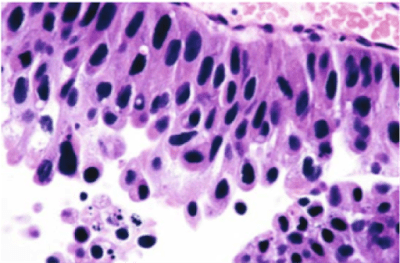

Característicamente, las células del CCT pueden aparecer solas o en pequeños racimos, y presentan grandes núcleos hipercromáticos con cromatina irregular de textura gruesa. Las células malignas identificadas mediante citología pueden clasificarse como:

- Las células desprendidas del CIS tienen un citomorfología similar a las lesiones invasivas de alto grado